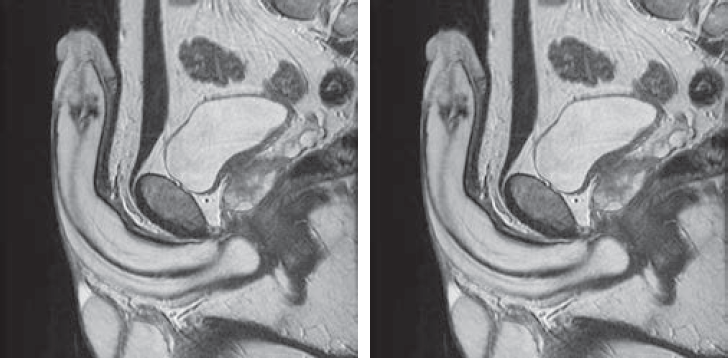

- ультразвуковое исследование (УЗИ) с использованием доплерографии сосудов полового члена (рис. 1, 2);

Рис. 1. Ультразвуковая доплерография сосудов полового члена в норме: а — 1, 2 (между стрелками) — половой член вне эрекции; 3 — кавернозные тела нормальной эхогенности; 4 (стрелки) — мочеиспускательный канал; 5 — мошонка; б — 1, 2 — половой член во время эрекции; 3 — кавернозные тела во время эрекции; 4 (стрелки) — мочеиспускательный канал; 5 — мошонка

Рис. 2. Ультразвуковая доплерография сосудов полового члена. Выделены кавернозные артерии